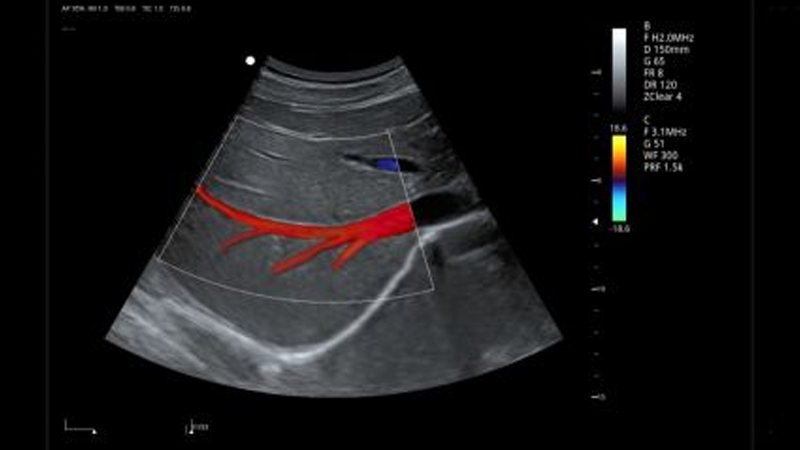

• Color Doppler-: This mode superimposes color on the regular gray-scale ultrasound image, representing blood flow direction and speed. Colors are assigned based on the direction of blood flow relative to the transducer. For example, red may indicate blood flow towards the transducer, while blue represents flow away from the transducer. Color Doppler allows for a quick visual assessment of blood flow patterns and abnormalities.